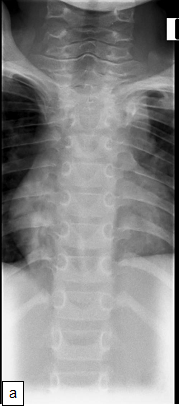

Chest X-ray (CXR): TB enlarged perihilar lymph nodes are better visualised on a lateral CXR than a PA view, therefore, it is important to obtain both PA and lateral films when evaluating a child with suspected TB.